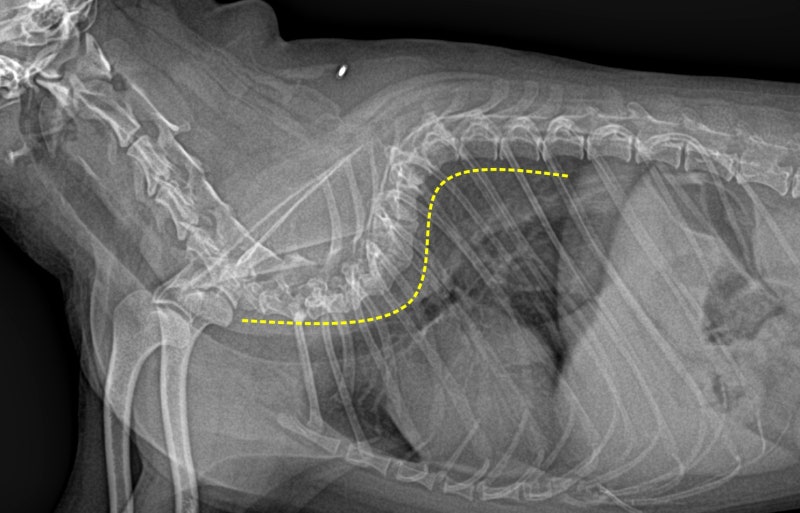

2. 기형 척추(Vertebral Malformation)

- 나비모양 척추(Hemivertebrae): 척추뼈가 한쪽만 자라 비틀어진 형태

- 척추가 S자형으로 휘거나 압박되어 신경 손상을 유발함

- X-ray(방사선 검사): 뼈의 구조적 이상 확인